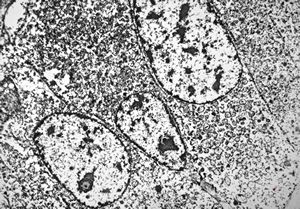

F, 68y. | APUD carcinoma mammae

F, 68y. | APUD carcinoma mammae - Bodian impregnation